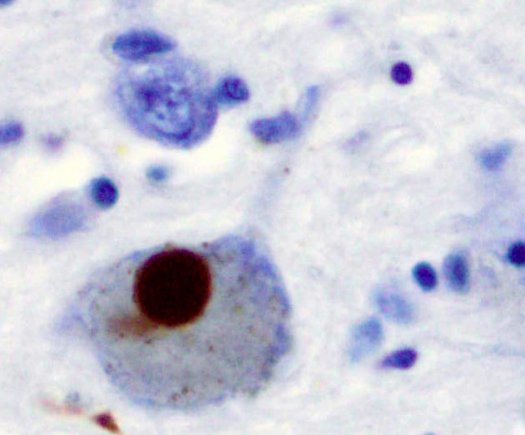

然而,冯健和他纽约大学布法罗分校的同事从四例患者包括(两例健康和两例携带帕金突变基因)身上提取皮肤细胞。他们诱导这些皮肤细胞成为多能干细胞,然后将其分化成神经细胞——具体来说,产生多巴胺的中脑神经细胞也称为多巴胺能神经元。

研究人员发现帕金基因会间接的损伤这些神经元。帕金基因调控血清单胺氧化酶(MAO)的合成,MAO则抑制神经传导物质多巴胺分泌。帕金基因突变时,调控作用丧失,MAO分泌增加,会导致分泌多巴胺的脑细胞受损。

Parkinson's disease (PD) is defined by the degeneration of nigral dopaminergic (DA) neurons and can be caused by monogenic mutations of genes such as parkin. The lack of phenotype in parkin knockout mice suggests that human nigral DA neurons have unique vulnerabilities. Here we generate induced pluripotent stem cells from normal subjects and PD patients with parkin mutations. We demonstrate that loss of parkin in human midbrain DA neurons greatly increases the transcription of monoamine oxidases and oxidative stress, significantly reduces DA uptake and increases spontaneous DA release. Lentiviral expression of parkin, but not its PD-linked mutant, rescues these phenotypes. The results suggest that parkin controls dopamine utilization in human midbrain DA neurons by enhancing the precision of DA neurotransmission and suppressing dopamine oxidation. Thus, the study provides novel targets and a physiologically relevant screening platform for disease-modifying therapies of PD.